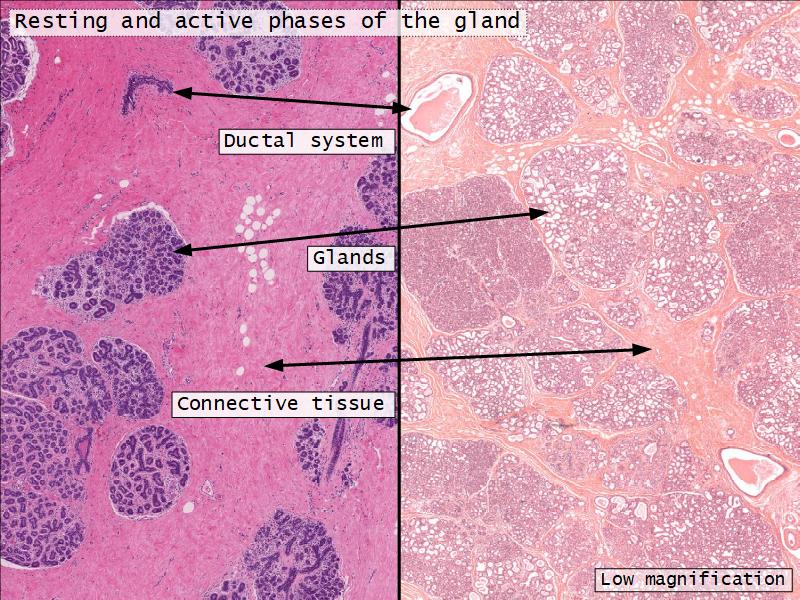

Resting and active

Describe the resting mammary gland and compare with the active gland.

(8)

Resting gland

- Connective tissue dominate

- More adipose tissue

- Glandular tissue reduced

Active gland

- Terminal ducts expand

- Forms alveoli

- Connective tissue reduced

- Adipose tissue reduced

- Glandular tissue dominate